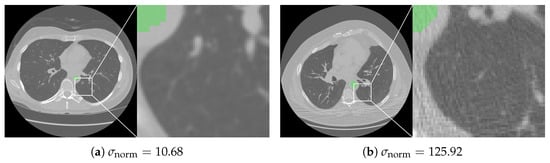

Low-Dose CT Quality Assurance at Scale: Automated Detection of Overscanning, Underscanning, and Image Noise

Automated quality assurance is essential for low-dose computed tomography (LDCT) lung screening, yet manual checks strain clinical workflows. We present a fully automated artificial intelligence tool that quantifies scan coverage and image noise in LDCT without user input. Lungs and the aorta are segmented to measure cranial/caudal over- and underscanning, and noise is computed as the standard deviation of Hounsfield units (HUs) within descending aortic blood, normalized to a 1 mm3 voxel. Performance was verified in a reader study of 98 LDCT scans from the National Lung Screening Trial (NLST), and then applied to 38,834 NLST scans reconstructed with a standard kernel. In the reader study, lung masks were rated ≥“Nearly Perfect” in 90.8% and aorta-blood masks in 96.9% of cases. Across 38,834 scans, mean overscanning distances were 31.21 mm caudally and 14.54 mm cranially; underscanning occurred in 4.36% (caudal) and 0.89% (cranial). The tool enables objective, large-scale monitoring of LDCT quality—reducing routine manual workload through exception-based human oversight, flagging protocol deviations, and supporting cross-center benchmarking—and may facilitate dose optimization by reducing systematic over- and underscanning. Full article